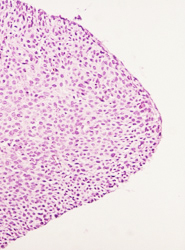

El resultado de una valoración colposcópica de paciente con lesión displásica siempre será confirmado por el estudio histopatológico que realiza el médico anatomopatólogo (estudio de la biopsia tomada en la colposcopía) . A continuación presentamos imágenes histológicas con sus diagnósticos.

• Lesión plana por VPH en vulva